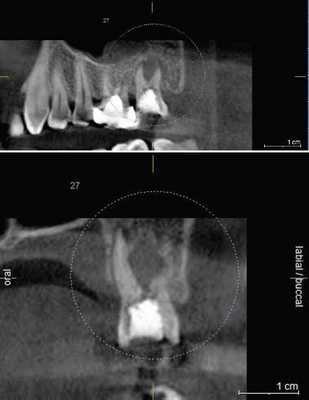

Рис. 1. При обследовании контактного пункта зубов 26, 27 (нижний фрагмент) кариес визуально не определяется; на сагиттальном реформате компьютерной томограммы в области проксимальных к контактному пункту поверхностей тех же зубов деминерализация очевидна.